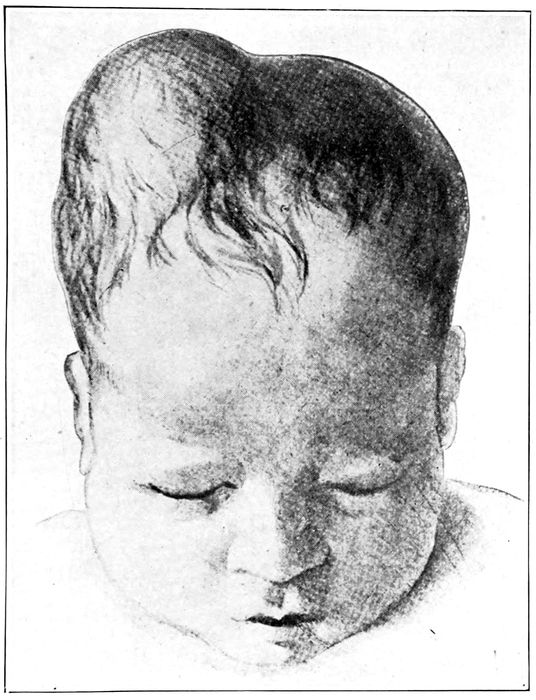

A cephalhæmatoma |

| |